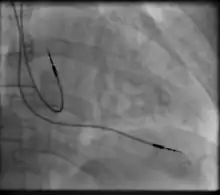

Transvenous pacing (temporary)

Transvenous pacing, when used for temporary pacing, is an alternative to transcutaneous pacing. A pacemaker wire is placed into a vein, under sterile conditions, and then passed into either the right atrium or right ventricle. The pacing wire is then connected to an external pacemaker outside the body. Transvenous pacing is often used as a bridge to permanent pacemaker placement. It can be kept in place until a permanent pacemaker is implanted or until there is no longer a need for a pacemaker and then it is removed.

Permanent transvenous pacing

Permanent pacing with an implantable pacemaker involves transvenous placement of one or more pacing electrodes within a chamber, or chambers, of the heart, while the pacemaker is implanted under the skin below the clavicle. The procedure is performed by incision of a suitable vein into which the electrode lead is inserted and passed along the vein, through the valve of the heart, until positioned in the chamber. The procedure is facilitated by fluoroscopy which enables the physician to view the passage of the electrode lead. After satisfactory lodgement of the electrode is confirmed, the opposite end of the electrode lead is connected to the pacemaker generator.